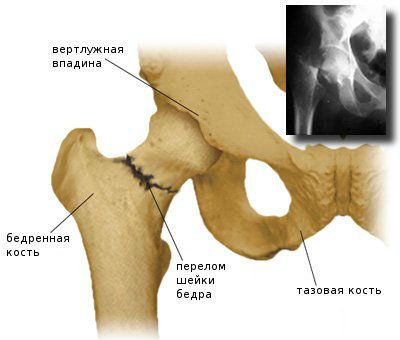

A második hely között a tünetek és komplikációk a csontritkulás egy törés a combnyak. Ez egy nagyon súlyos trauma, amely kapcsolatban van egy nagy a kockázata a rokkantság és a korai halálozás. Kap egy nagyon egyszerű törés. Élesen ahhoz, hogy felálljon a láb esik az oldalra, ugrik, és így tovább.

csípőtörés - komoly következménye a csontritkulás, ami a fogyatékosság és korai halált